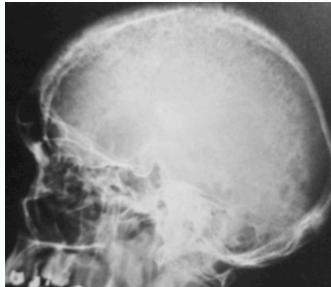

- Skull: âsalt & pepperâ appearance

Treatment

Salt-and-pepper-spots-in-skull